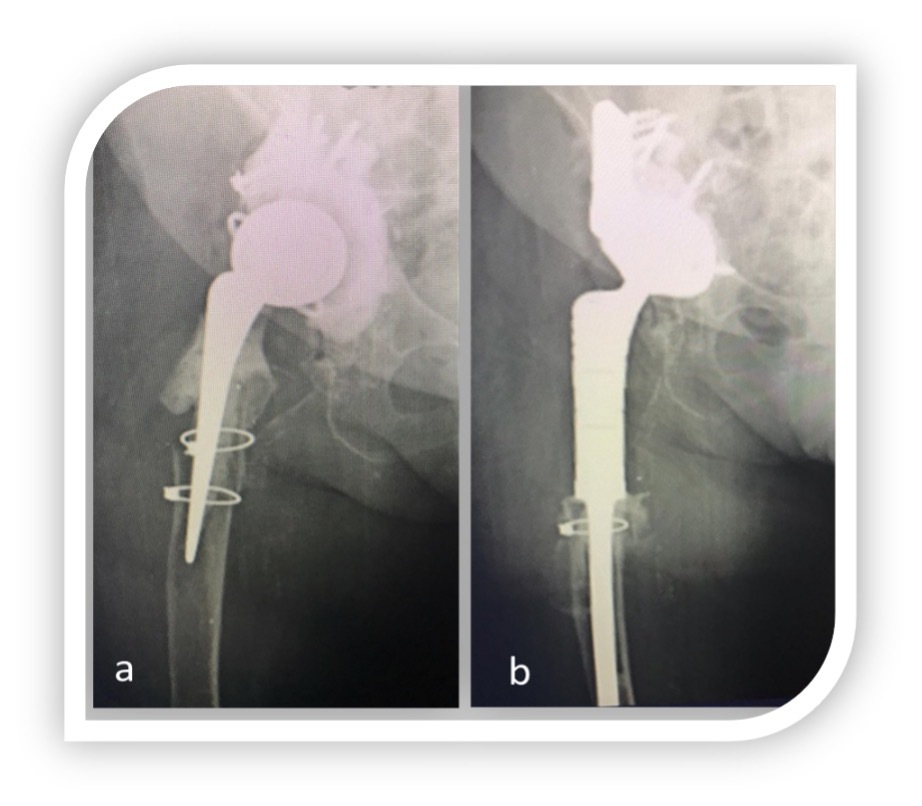

All complications occurred during the first-year follow-up. We recorded eight complication (8/39 patients, 20%): one transient paralysis of the external popliteal nerve, during perioperative time, resolved at the end of the third month; three surgical site infections managed with debridement, washing of the wound and antimicrobial therapy; two dislocation and two periprosthetic fracture and dislocation, in these cases acetabular component was revised with a retentive cup (constrained liners).

At last follow-up all implants were osteointegrated even in presence of thin striae of femoral radiolucency in most reported cases. In particular 16 radiolucency were noticed (3 in periprosthetic fractures, 7 in periprosthetic osteolysis and 6 in recalcitrant infections). No patients showed clinical symptoms related to radiolucency.